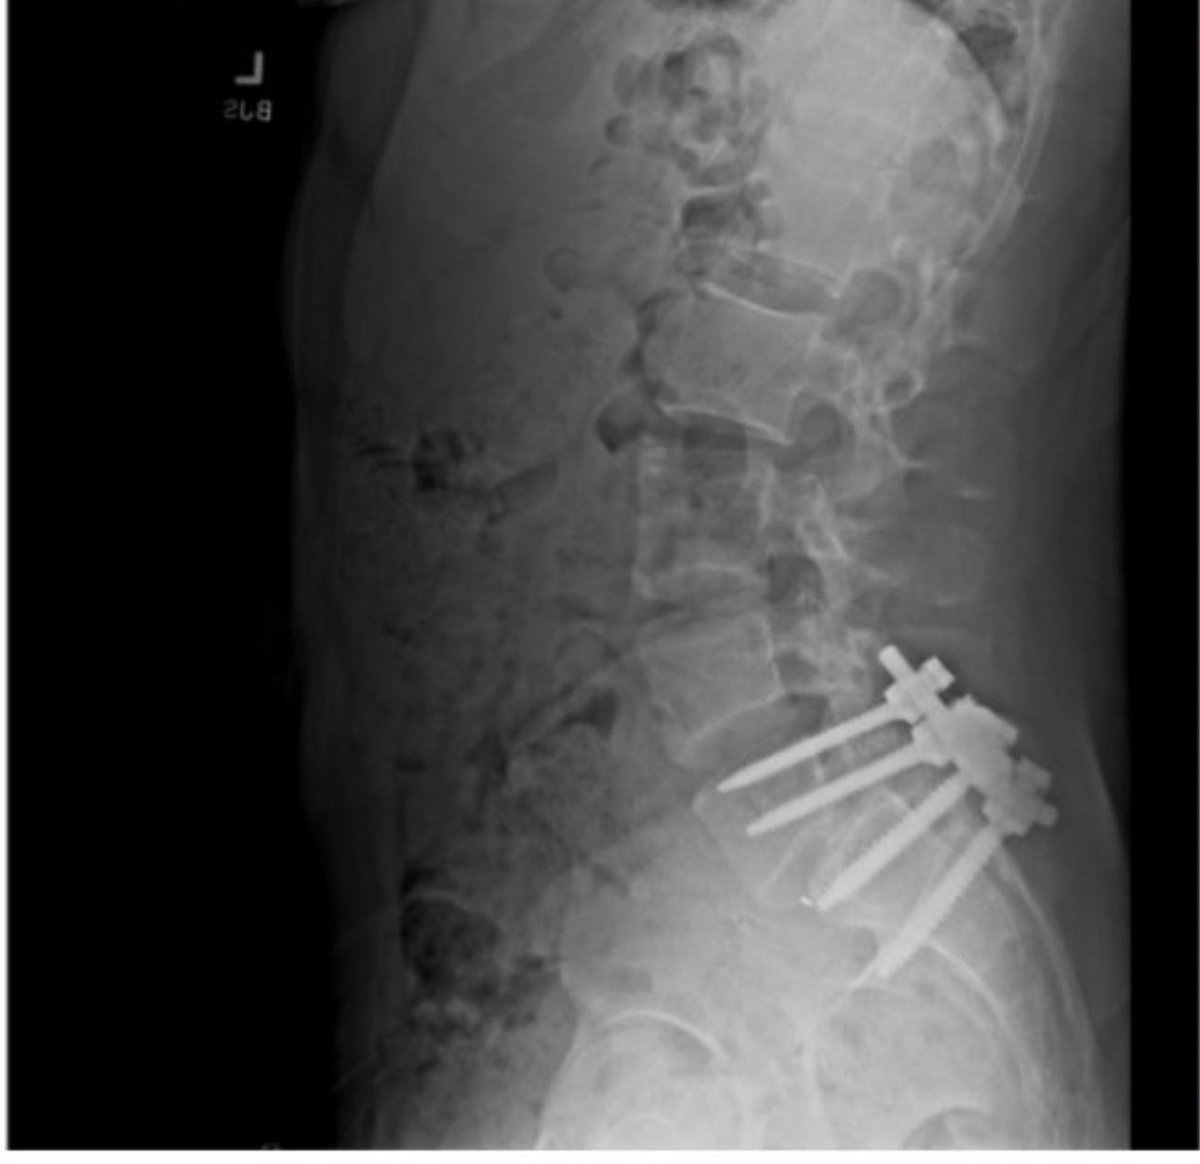

This is the lumbar spinal xray posted on Luigi Mangione's Twitter profile. It shows he had a spinal fusion surgery (the screws at the bottom), along with some degenerative changes that you'd normally see in a later middle-aged person, but could also be present in a younger person who's had a serious injury.